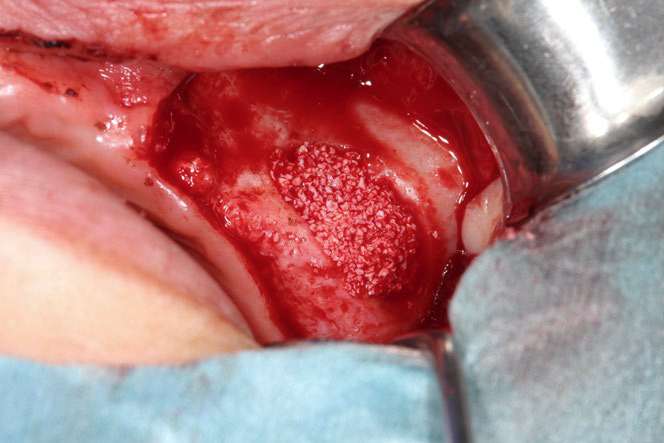

GBR法の手術の流れを写真でご紹介しています。

どのような手術を行うのか、事前に知っていただけたらと思います。

この際に行うのが、上顎洞底挙上術(サイナスリフト)です。

サイナスリフトでは上顎洞側に人工骨の粉末を入れ、上顎洞側に骨の再生を誘導します。

サイナスリフトの手術の流れを写真でご紹介しています。